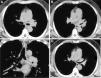

(A–C) CT from diagnostic study, showing considerable thickening of the left main bronchus, extending to the upper left lobe bronchus. A soft tissue mass is seen protruding into the lumen of the upper lobe bronchus. (D) Follow-up CT, 2 months after treatment, showing reduced thickening in the wall of the left main bronchus and left upper lobe bronchus, and resolution of the soft tissue mass that was invading the left upper lobe bronchus.

We report the case of a 52-year-old man with a diagnosis of acute myelomonocytic leukemia, receiving his second consolidation chemotherapy. He was admitted for fever and productive cough, after receiving inhaled colistin for one month for multidrug-resistant Pseudomonas aeruginosa respiratory tract colonization. We decided to suspend chemotherapy and started a diagnostic study. The chest X-ray showed no significant changes and the blood panel showed hemoglobin 10.8g/dl, leukocytes 7.7×103μ/l and 69% neutrophils. A repeat sputum culture was positive for multidrug-resistant Pseudomonas aeruginosa, so colistin treatment was maintained. In view of persistent symptoms, a chest computed tomography (CT) was performed, revealing parietal thickening of the carina and the left main bronchus, extending to the upper left lobe bronchus, and partially to the left lower lobe bronchus. A soft tissue mass was seen protruding into the lumen of the upper lobe bronchus (Fig. 1A–C). Pulmonary parenchyma was unchanged (Fig. 1).

In an immunosuppressed patient, the first diagnosis to consider is fungal infection (aspergillosis, candidiasis or mucormycosis). Fiberoptic bronchoscopy was performed, which showed whitish membranes in the trachea and in both main bronchi. Biopsies were obtained and were found to contain fibrinous, inflammatory membranes and fragments of bronchial mucosa with mature squamous metaplasia and neovascularization, with no evidence of malignancy. Aspergillus fumigatus was isolated from the culture of the biopsy samples, and treatment began with voriconazole, with gradual resolution of fever and cough. The follow-up CT, 2 months after treatment, showed reduced tracheobronchial wall thickening (Fig. 1D).